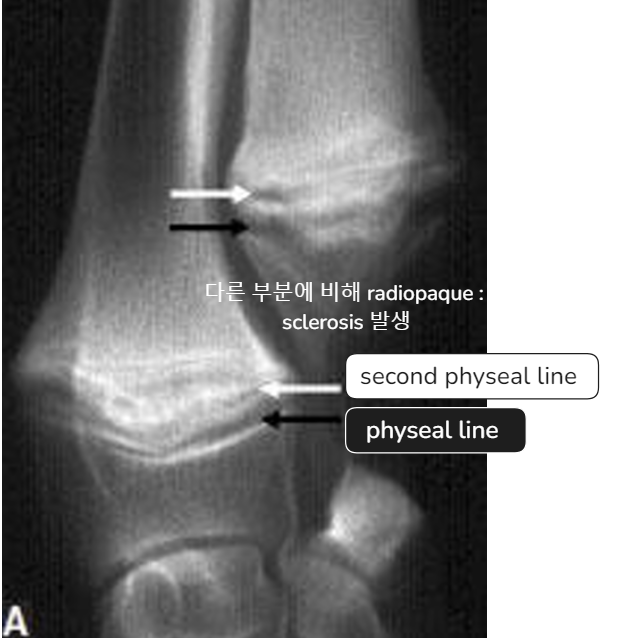

| - 아래쪽만 양옆으로 커지면서 flaring 양상을 보임. | Early sign - Metaphyseal soft tissue swelling | 비정상적인 periosteal reaction이 심하게 나타남, 성장판도 손상 받음 |

- Physeal line의 손상이 심해 각기형? 등 문제가 될 수 있음.